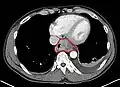

Additional testing is needed to assess how much the cancer has spread (see § Staging, below). Computed tomography (CT) of the chest, abdomen and pelvis can evaluate whether the cancer has spread to adjacent tissues or distant organs (especially liver and lymph nodes). The sensitivity of a CT scan is limited by its ability to detect masses (e.g. enlarged lymph nodes or involved organs) generally larger than 1 cm.[43][44] Positron emission tomography is also used to estimate the extent of the disease and is regarded as more precise than CT alone.[45] PET/MR as a novel modality has shown promising results in preoperative staging with fair feasibility and good correlation in comparison to PET/CT. It can enhance tissue differentiation with lowering the radiation dose to the patient.[46] Esophageal endoscopic ultrasound can provide staging information regarding the level of tumor invasion, and possible spread to regional lymph nodes.

Contrast CT scan showing an esophageal tumor (axial view)